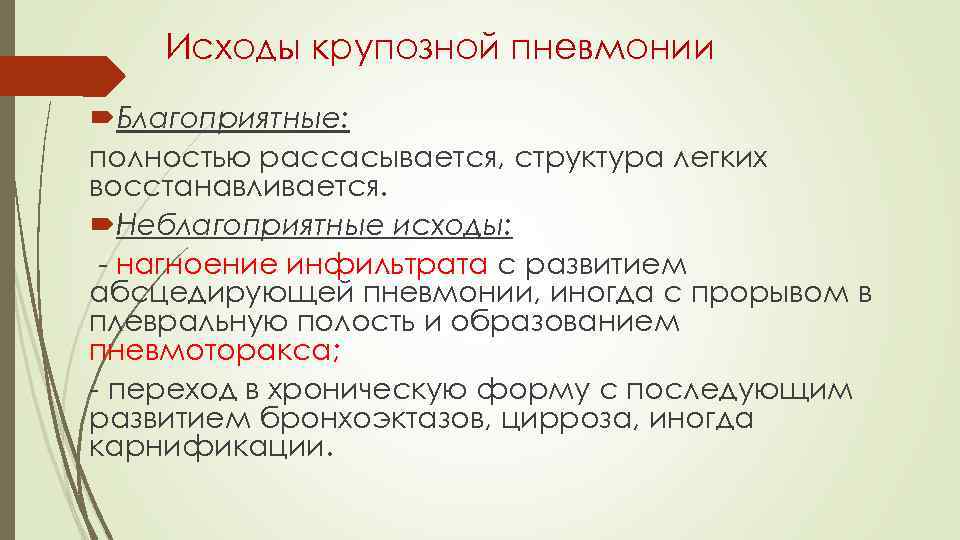

Острая внебольничная пневмония по МКБ-10: признаки и примеры